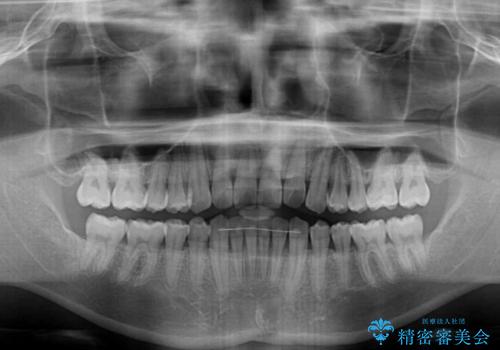

- 前歯のデコボコを気にして来院された患者様です。

主に下顎歯列全体の後方移動とIPR(歯と歯の間を削る)によってデコボコが解消するように設計し、インビザラインにより治療を行うこととしました。

インビザライン矯正特有の、治療後半で前歯のみが強く接触する症状が発現し、咬み合わせ改善に期間を要することとなりました。